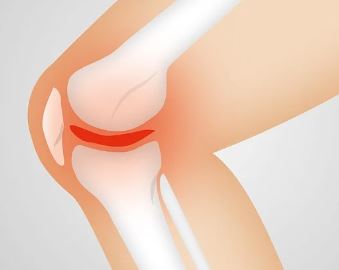

골관절염은 무릎 관절에서 가장 흔하게 발생하는 형태의 관절염입니다.

관절을 보호하는 연골이 마모되면서 뼈와 뼈가 직접 마찰하게 되어 통증이 발생합니다. 주로 중년 이후에 발생하지만, 과체중이나 과거의 무릎 손상으로 인해 젊은 사람들에게도 나타날 수 있습니다.

초기에는 운동 후 또는 아침에 무릎이 뻣뻣하고 아픈 증상이 나타납니다. 치료 방법으로는 체중 감량, 물리치료, 약물 치료, 그리고 심한 경우에는 수술적 치료가 고려될 수 있습니다.